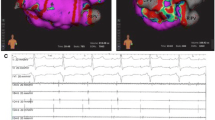

Samples came from freshly slaughtered pigs, and left atria were isolated to be employed in the present study. Concerning the sections done by the personal of the company while slaughtering the animals, the lesions were performed in the left atrium inferior posterior wall, on the broad junction (difference of species with human left atrium) [8], to the pulmonary venous compartment avoiding when possible the pectinate muscles (Fig. 3).

After being washed to remove the residual blood with NaCl (B. Braun, Melsungen, Hessen, Germany), they were put into a transport medium RPMI 1640 (Sigma-Aldrich, St. Louis, MO, USA). Samples were randomly assigned to two groups of study: (1) simultaneous biparietal bipolar (SBB), where the poles were placed on the opposite sides of the sample and the radio frequency crossing the sample width, and (2) simultaneous uniparietal bipolar (SUB) mode, where the electrodes were placed on only a side of the sample (Fig. 4). Twenty samples of each group were employed for a total of 40 samples.

No audible steam pops were encountered during the procedure, and no perforations were observed. The slices obtained formed a progressive sequence where modification of the shape of the lesion was appreciated (Fig. 5).

Progressive slice sequence. Ablation lesion formation progression while slicing the samples perpendicular to the direction of the catheters. The numbers show the lesion shape and dimensions in the study groups at that particular number of the slice pack. The SBB group shows a continuity of the lesions throughout the thickness of the sample. The SUB group shows a discontinuity in the progression of the lesion

Both the intra- and interobserver variabilities for the measurement of DEPI (k = 0.97, k = 0.91, respectively) and ATOT (k = 0.95, k = 0.89, respectively) were low, indicating an excellent repeatability and reproducibility of the measurements. Samples showed a thickness of 4.36 ± 0.20 mm in SBB and 4.20 ± 0.20 mm in SUB, with no significant difference (p > 0.05). Transmural lesions were detected in 18 samples over 20 (90%) in SBB group, while in SUB, transmural lesions were present in 9 samples over 20 (45%) (Fig. 6).